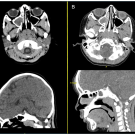

Justin Lien, BS; Ananya Narasimhan, BS; Nicholas Basalous; Evan M. Masutani, MD, PhD; Mariam Fahim, DO

A 6-year-old boy with a past medical history of recurrent otitis media presented to an outpatient pediatrician for subacute new-onset headache and photophobia.